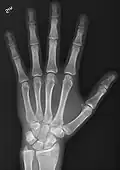

- Hand - DP and Oblique

-

Left hand by dorsoplantar projection -

Lateral projection -

Oblique projection